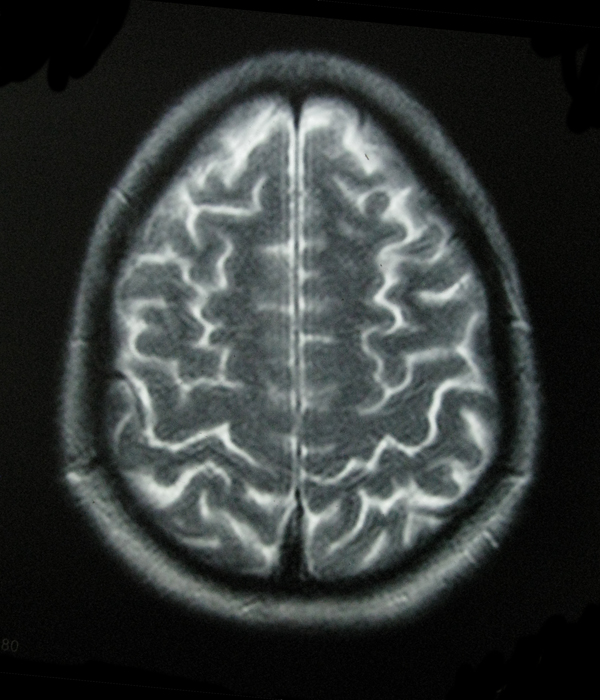

- My Brain in 2009